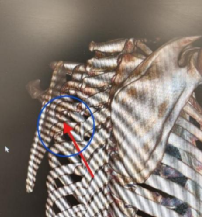

患者需手术的肋骨骨折断点位于肩胛骨深面,且患者肩胛骨已有骨折(见图三、图四)。如果进行传统的肋骨骨折内固定手术,需要切开肩胛骨周围大量肌肉层次,手术带来的创伤较大;

更为关键的是传统的肋骨骨折内固定手术需要使用医疗器械“掀开”肩胛骨才能显露手术区域,患者肩胛骨已经存在骨折(目前肩胛骨的骨折是不需要手术的),手术过程中有可能加重肩胛骨的骨折,最终可能导致肩胛骨的骨折也需要去做内固定手术。

图三 图四